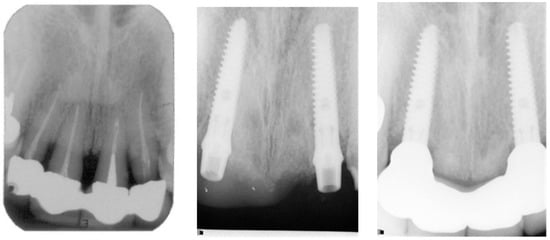

Figure 9.

Radiographs taken before treatment, at transfer verification, and 40 months after bridge installation. (patient No. 29).